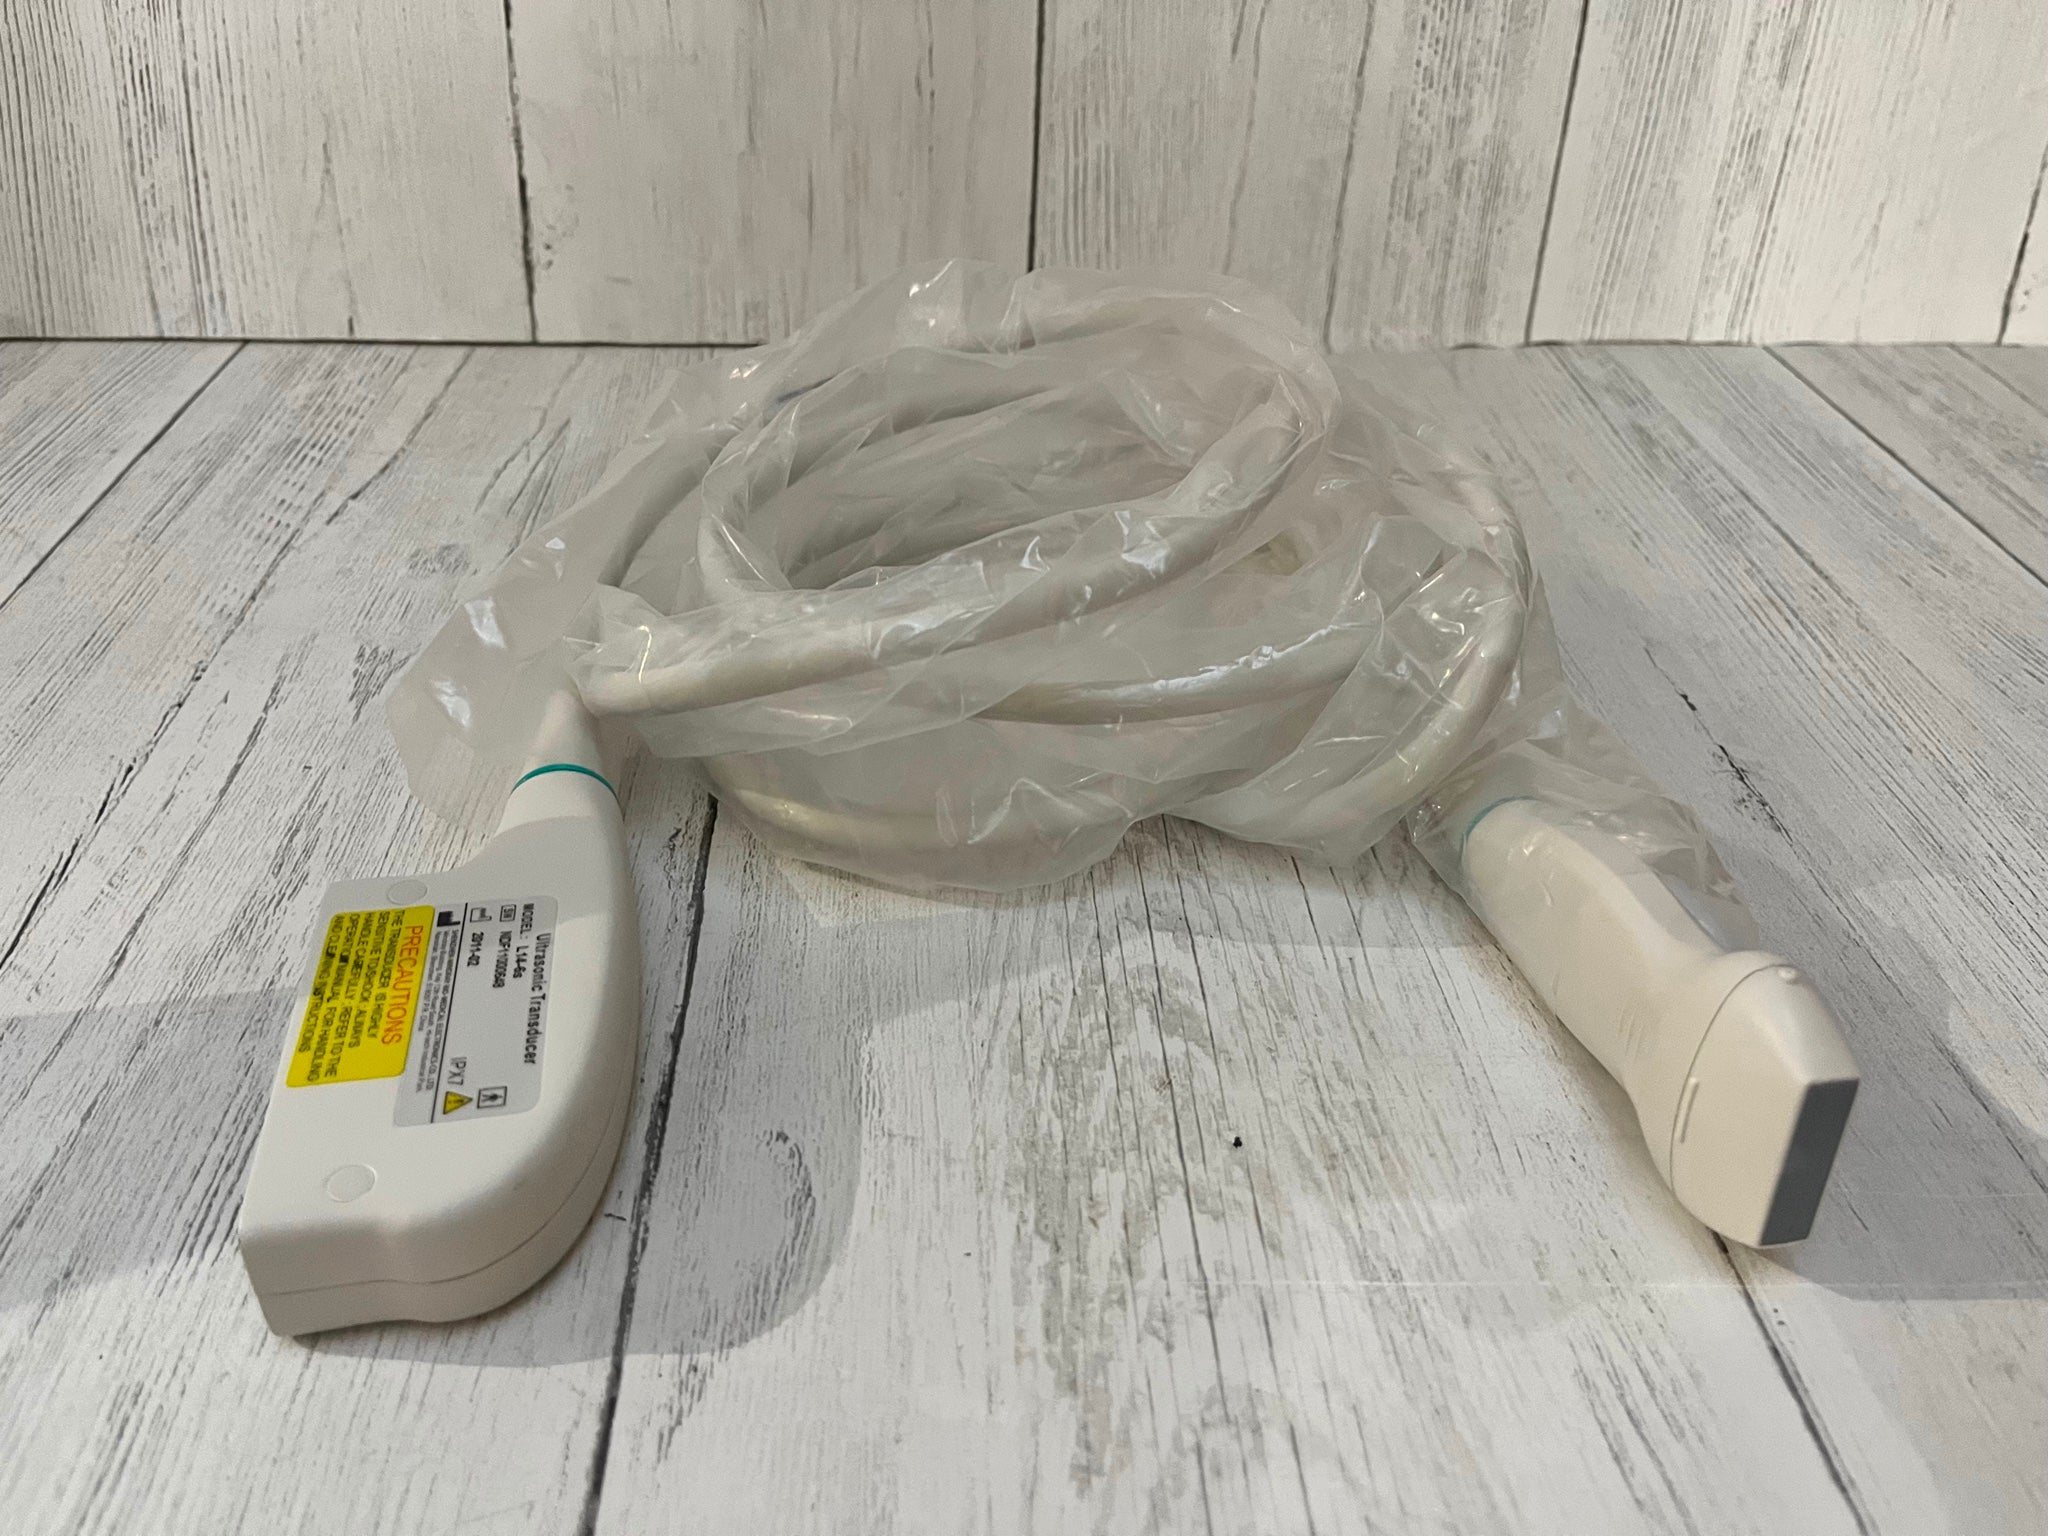

Probe Function: 3.5MHZ convex, abdominal organs

Probe 2: 7.5MHZ Transvaginal probe:gynecologic examination

The Diagnostic Ultrasound Scanner is an advanced medical device that uses high-frequency sound waves to create precise images of the body's internal structures. This technology plays an important role in diagnostics because it helps healthcare professionals identify issues such as abnormalities in organs and tissues, leading to early intervention. The incorporation of a Convex and Transvaginal Probe offers versatility, making it suitable for various examinations. Using this ultrasound scanner, doctors can provide better care and ensure patient satisfaction.